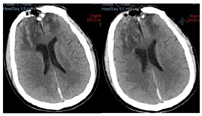

头颅CT(图1)提示:双侧额叶脑挫裂伤并出血术后状态;颅骨CT三维成像(图2)提示:额骨骨质缺损,额窦壁、右侧眼眶内壁、上颌窦壁等多处骨折。脑脊液检查结果:葡萄糖<1.0 mmol/L,乳酸5.62 mmol/L,氯106.7 mmol/L,蛋白质1.19 mmol/L,白细胞计数(white blood cell count,WBC)83×106/L。

患者于伤后当天(2021年7月29日)在当地医院急诊行"颅内血肿清除术+凹陷性粉碎颅骨骨折清除术",术后持续出现脑脊液鼻漏,伴伤口渗液,持续昏迷,GCS评分E1VTM3。患者于2021年8月3日转入我院,于2021年8月5日在全麻下行"颅骨骨折整复+脑脊液漏修补术",开颅探查前颅底进行重建修补,额窦及筛窦存在裂缝,封填额窦和筛窦,并取大腿部部分阔筋膜、少量脂肪和肌肉填塞,术中见额部硬膜存在缺损,以人工脑膜进行严密缝合,留置皮下引流管,术后第3天引流量少,皮下引流管拔除。术后观察患者未再出现脑脊液漏。术后仍为昏迷状态,住院期间,间断出现发热,热型表现为不规则热。2021年8月8日行腰椎穿刺术并留取脑脊液检查,提示:WBC:83×106/L,葡萄糖<1.0 mmol/L,乳酸5.62 mmol/L,氯106.7 mmol/L,蛋白质1.19 mmol/L;脑脊液培养结果为:鲍曼氏不动杆菌;痰涂片可见革兰阳性球菌、阴性杆菌;考虑颅内感染并呼吸道感染。根据药敏结果给予以替加环素100mg、每12小时1次,联合万古霉素1.0g、每12小时1次抗感染治疗。患者仍存在持续高热,2021年8月10日行"腰大池置管外引流术",有黄色透明脑脊液流出,复查脑脊液结果提示:WBC:37×106/L,蛋白质1.18 mmol/L。2021年8月12日呼吸道标本培养提示:鲍曼氏不动杆菌,调用抗生素为多黏菌素50u、每12小时1次,联合替加环素100mg、每12小时1次,利奈唑胺600mg、每8小时1次,治疗呼吸道感染及预防革兰阳性球菌所致颅内感染。2021年8月16日患者意识呈昏迷状态,刺激能睁眼,体温间断高热,腰大池引流不通畅给予拔除。头部伤口愈合差,有少量脓性渗出,若进一步发展,有加重颅内感染可能,头部伤口给予留置VSD(图3)辅助伤口愈合。抗生素应用方案为多黏菌素50u、每12小时1次,替加环素100mg、每12小时1次,利奈唑胺600mg、每8小时1次。2021年8月17日复查脑脊液结果提示:WBC:350×106/L,蛋白质2.37 mmol/L,2021年8月19日患者呈浅昏迷状态,刺激可睁眼,患者痰培养、血培养、伤口分泌物培养均未见菌种生长,停用替加环素。体温较前稳定,感染基本控制。2021年8月24日复查脑脊液结果提示:WBC:8×106/L,蛋白质0.7 mmol/L,细菌培养未检出。查血清G试验结果为阴性GM试验<0.5 µg,肺泡灌洗液细菌培养未见菌种生长。复查头部CT示双侧额叶出血及水肿较入院时吸收,硬膜下少量积液(图4)。患者意识状态较前改善,回当地医院继续康复及支持治疗。